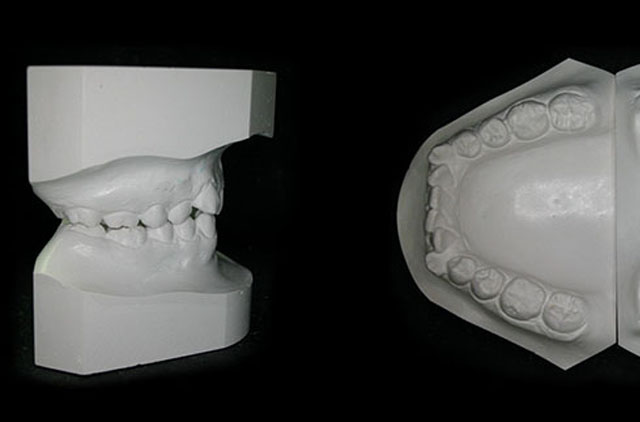

-Modelos de Estudio en yeso con caja plática rígida

Modelos de Estudio

Modelos de Estudio en Yeso, CAJA DE PLASTICO (rigida)

Modelos de estudio en Acrílico 1 color, CAJA DE PLASTICO (rigida)